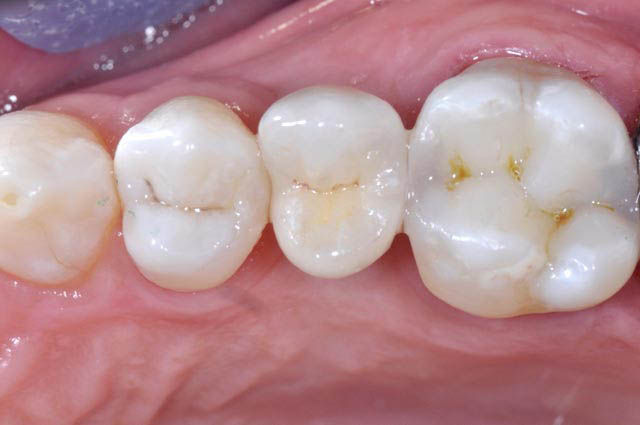

Clinical control and radiograph after 3 years, attesting the stability of the results over time.